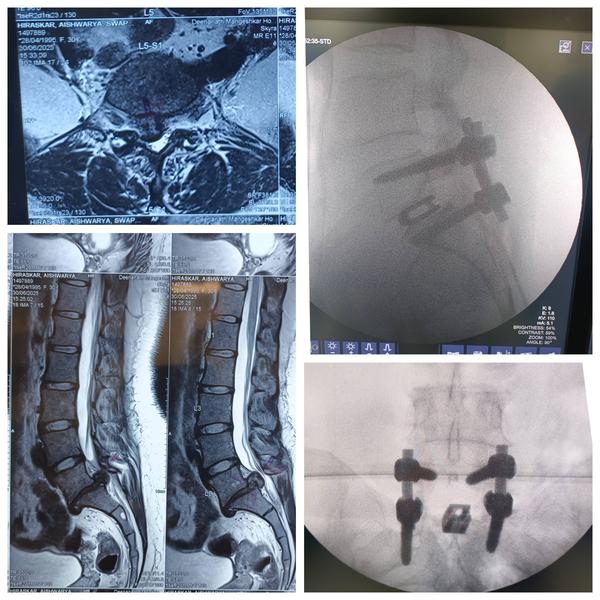

L3-L4, L4-L5 DISC PROLAPSE, SEVERE SPINAL CANAL STENOSIS –SPINAL FIXATION & DECOMPRESSION DISCECTOMY